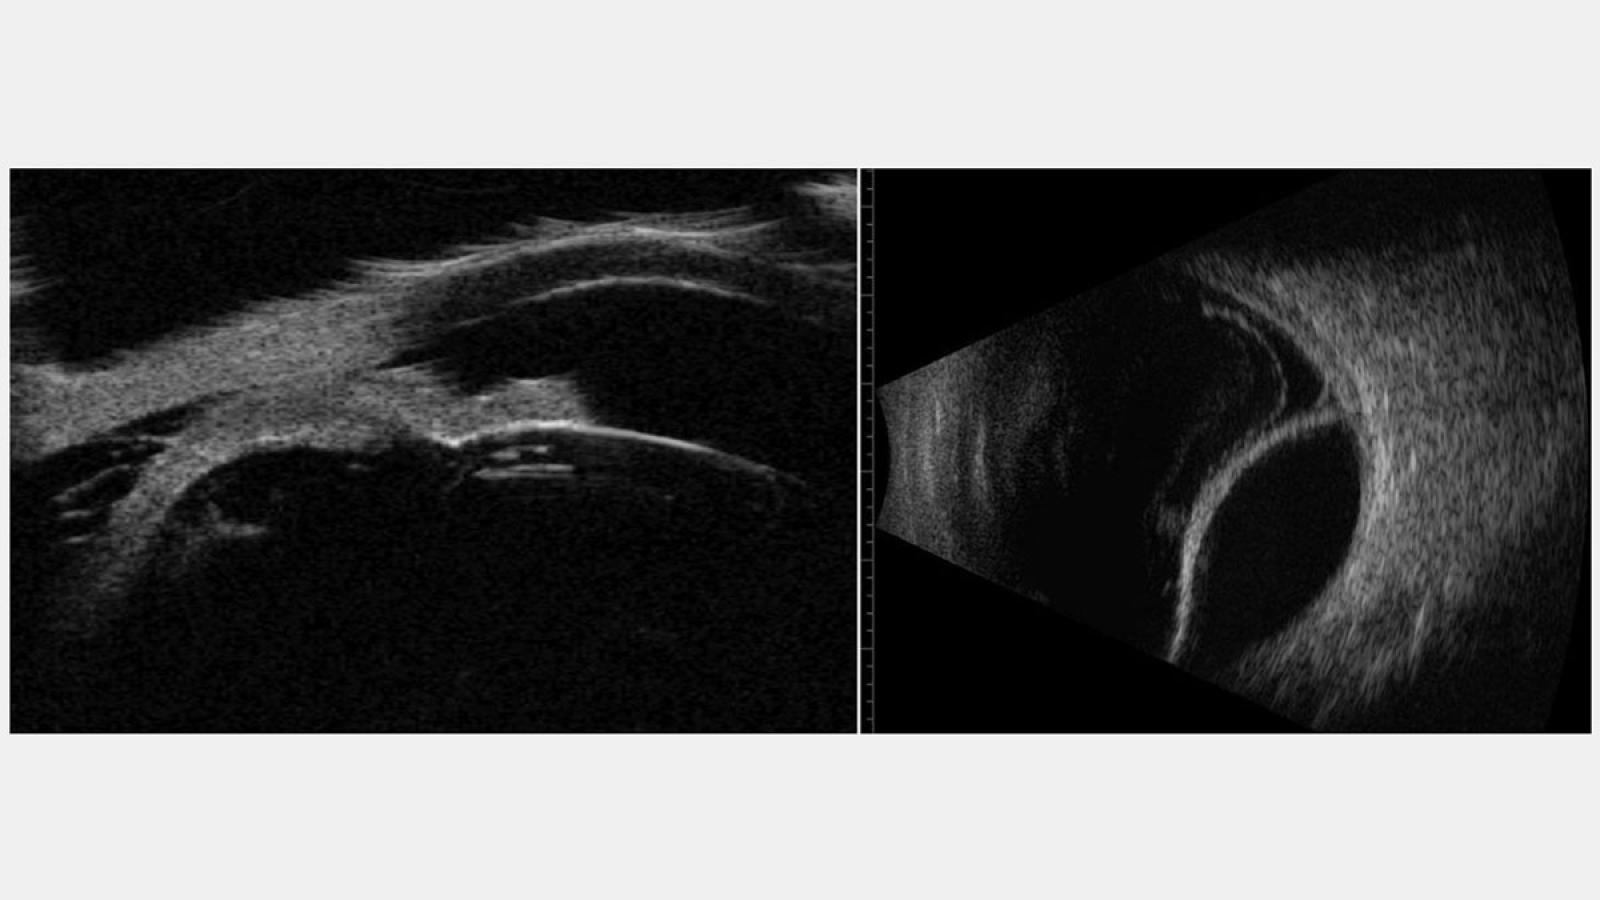

Dr. Silverman has been involved in ultrasound research in ophthalmology for over 30 years. His research includes development of high-resolution imaging systems, studies of ultrasound safety and bioeffects, high-intensity ultrasound, blood-flow imaging, photoacoustics, and tissue characterization by use of signal-processing. He applies these techniques for studies of ocular disease in animal models and for clinical examinations.

Dr. Silverman is currently Principle Investigator on an NIH-sponsored project whose goal is development of a novel ultrasonic imaging technique, ultrafast plane-wave imaging, which enables acquisition of up to 10,000 images per second. Computer-analysis of the data allows visualization and measurement of blood-flow throughout the eye and orbit. This technique is being applied to glaucoma, vascular malformations and occlusions, and retinopathy of prematurity. Technical collaborators on this project include Raksha Urs, PhD, Jeffrey Ketterling, PhD (Riverside Research) and Alfred Yu, PhD (University of Waterloo).